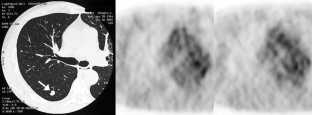

Fig. 1

Fig. 2

Fig. 3